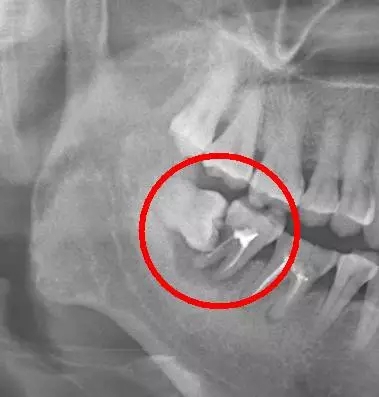

口說無憑,上病例。來看下面這例

640.webp (4).jpg

這種情況就因為沒及時拔除智齒,最終的結(jié)果就是把鄰牙也拖下水,兩顆牙齒一起報銷,旁邊的第二恒磨牙本來就容易因為清潔不徹底齲壞的好么,還要無端被拖著陪葬,真是生存不易。更慘的是,鄰牙拔除之后,還必需要裝上一顆種植牙補(bǔ)上(我會告訴你裝一顆種植牙花費上萬是很正常的么),得不償失啊?。?/span>

需要特別注意的是,鄰牙病變具有一定的隱蔽性,通常的情況是可能旁邊牙齒已經(jīng)被頂壞了,患者還沒有任何感覺,這就需要拍一張口腔 X 光片才能進(jìn)行準(zhǔn)確的診斷。